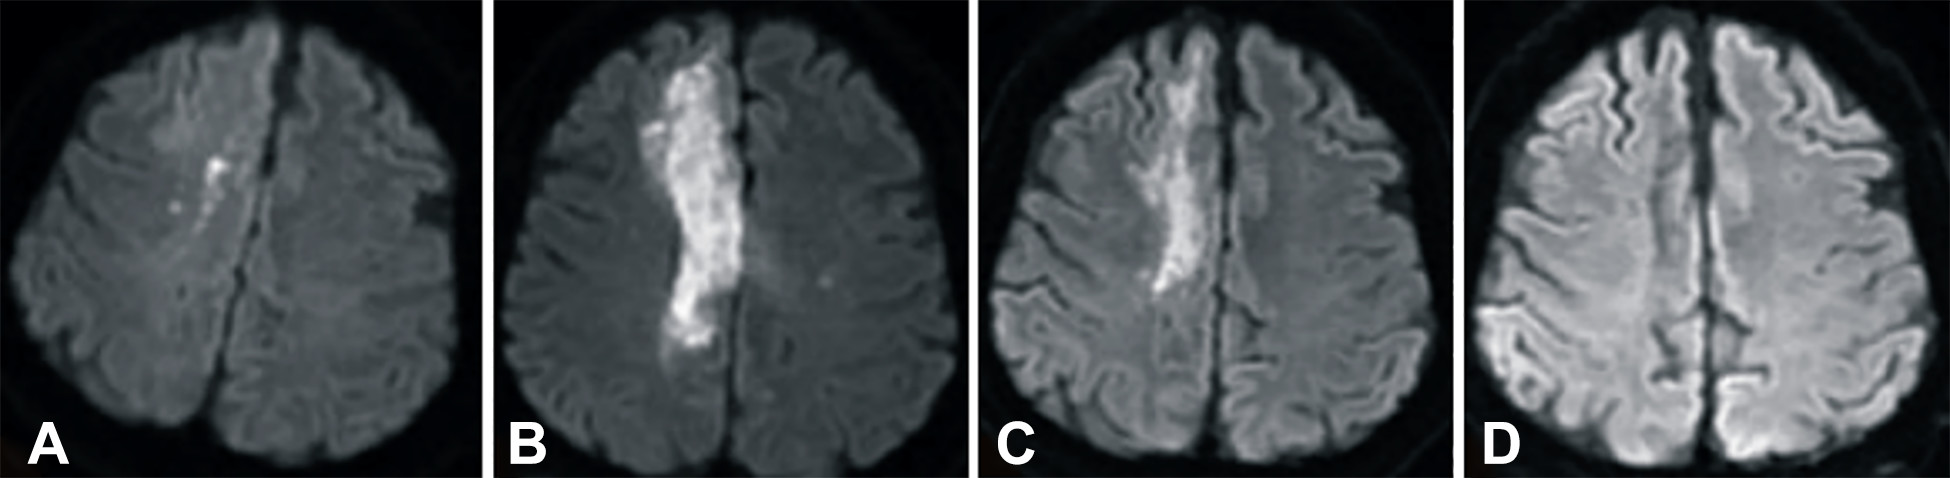

發(fā)病后2小時(shí)和8天行彌散加權成像(DWI)檢查,發(fā)現右側放射冠梗塞(白色信號增加),3個(gè)月后梗塞散在,6個(gè)月后消失(圖2A-D)。

卒中發(fā)病后2小時(shí)和單核細胞臍帶血輸注后6個(gè)月獲得的彌散加權圖像

圖2 . 卒中發(fā)病后2小時(shí)和單核細胞臍帶血輸注后6個(gè)月獲得的彌散加權圖像。(A)卒中后2小時(shí),(B)臍帶血輸注后1天,(C)臍帶血輸注后3 個(gè)月,(D)單核細胞輸注后6個(gè)月